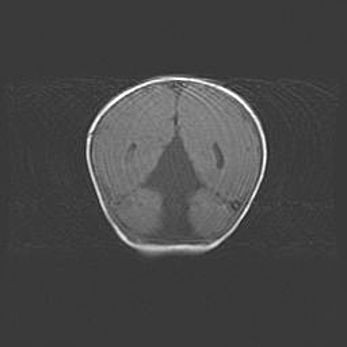

Множественные кисты обоих полушарий головного мозга, наибольшая из них в правой затылочной области. Ассиметричная атрофическая гидроцефалия.

Возраст: 7 месяцев

Вес: 5660 г

Пол: мужской

Окружность головы: 41,5 см

Срок гестации: 28-29 недель

Кисты головного мозга развиваются в результате многоочаговых некрозов вещества мозга и возникают вследствие перенесенной перинатальной инфекции, менингитов, энцефалитов, асфиксии, родовой травмы, расстройств мозгового кровообращения различного генеза. Образованию кист в веществе головного мозга плодов и новорожденных способствуют такие факторы, как высокое содержание в нем воды, недостаточная (или отсутствие) миелинизация и слабая астроглиальная реакция на повреждение.

Кисты могут сочетаться с гидроцефалией и другими поражениями головного мозга.